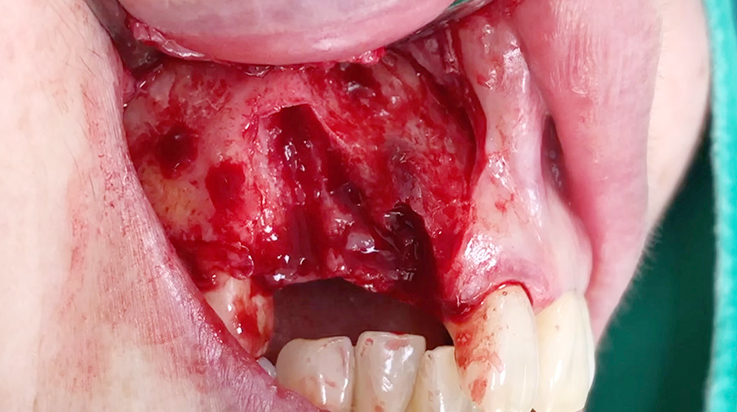

A surgical procedure using non resorbable membrane

• A surgical procedure using non resorbable membrane 1